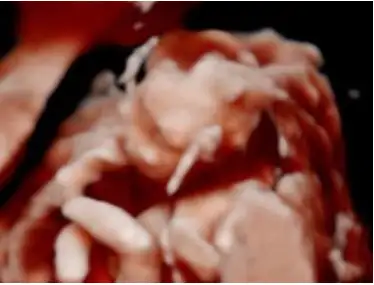

Dertli çoçuğumun fotoğrafını da paylaşayım. Dün 1,5 saat boyunca düşünür moddaydı

Yaaaa annesi neden dertli diyorsun ki? Dün doktorum bana "Filozof olacak bu" dedi. Benimki de sürekli düşünüyor. Şimdi doktorun verdiği usg videolarını izliyorum. Aman Allah'ım içimde resmen bir dünya var! Allah bize nasıl bir şey bahşetmiş, kafayı yememek elde değil. Minyatür insan!

Kızarsınn diye yazamadım dün canım. Ama bugün tutamayacağım bana erkek gibi geliyorYaaaa annesi neden dertli diyorsun ki? Dün doktorum bana "Filozof olacak bu" dedi. Benimki de sürekli düşünüyor. Şimdi doktorun verdiği usg videolarını izliyorum. Aman Allah'ım içimde resmen bir dünya var! Allah bize nasıl bir şey bahşetmiş, kafayı yememek elde değil. Minyatür insan!

Ben çocuğumu ekran fotoğrafı yaptım. Çok tatlılar ya gözlerim doldu yineYaaaa annesi neden dertli diyorsun ki? Dün doktorum bana "Filozof olacak bu" dedi. Benimki de sürekli düşünüyor. Şimdi doktorun verdiği usg videolarını izliyorum. Aman Allah'ım içimde resmen bir dünya var! Allah bize nasıl bir şey bahşetmiş, kafayı yememek elde değil. Minyatür insan!

Ben çocuğumu ekran fotoğrafı yaptım. Çok tatlılar ya gözlerim doldu yine